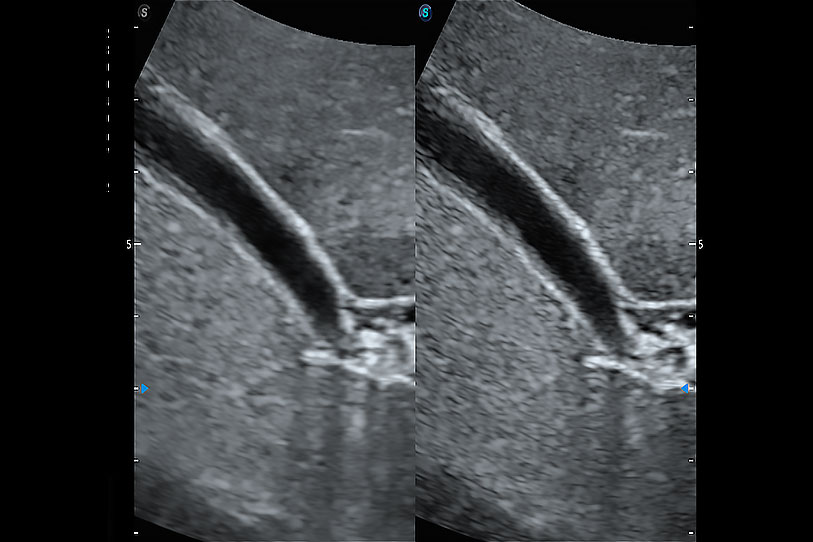

增強(qiáng)穿刺針在動物解剖結(jié)構(gòu)中的位置,提高穿刺介入的安全性和準(zhǔn)確性。